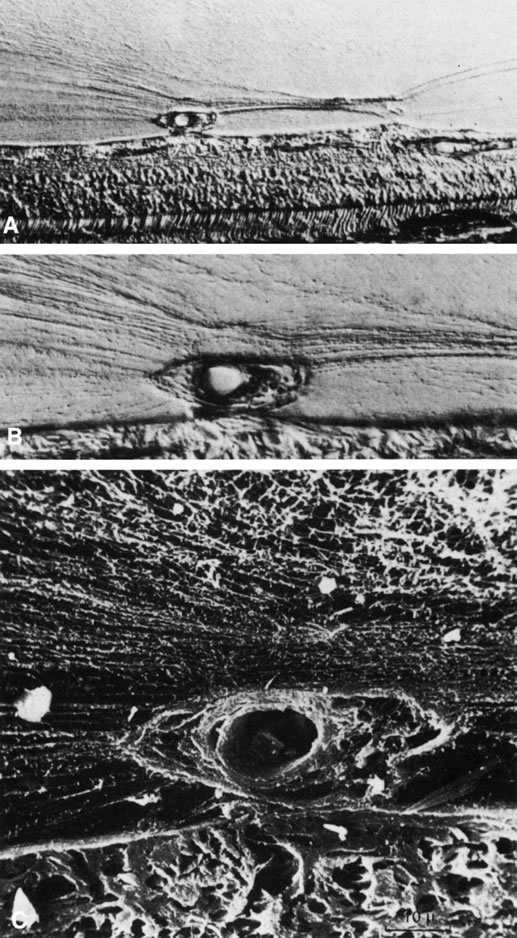

In 1957, Teng and Chi145 claimed that “irregularities” of the vitreous base are responsible for the vitreoretinal traction that results in peripheral retinal tears. It is known that at the vitreous base, there are collagen fibrils oriented perpendicular to the wall of the eye,138,139,146 with insertions anterior and posterior to the ora serrata.82,147 Gartner100 found that with aging, there is aggregation of the collagen fibrils of the vitreous base similar to the aggregation of collagen fibrils seen within the central vitreous.84 Various conditions of the peripheral retina that are associated with increased vitreoretinal traction include meridional folds, peripheral pigment clumps, retinal rosettes, granular patches, and progressive lattice-like degeneration.144–152 Recently, two structures have been identified (Fig. 10) that are probably remnants of the fetal vasculature in the primary vitreous and are likely to play a role in transmitting traction to the peripheral retina.153

Fig. 10. A. Cystic retinal tuft. The tuft is a cystoid formation of fibers, similar to those of the nerve fiber layer, and cells similar to those found in the inner plexiform layer of the retina. The tuft is connected to the internal limiting lamina of the retina. This scanning electron micrograph shows the insertion of the vitreous collagen fibers on the tuft's apical surface. Their orientation changes toward the tuft's surface. B. Verruca. The verruca has a structure similar to that of a tree. Its “roots” are embedded in the inner layers of the retina. Cellular elements resembling cells of the inner plexiform layer can be seen near the retinal surface. The “trunk” of this structure extends from the retina to the middle parts of the vitreous cortex. The “branches” of the verruca are intertwined with interrupted vitreous collagen fibers. Local condensation of collagen fibers exists as well as local collagen destruction (arrows) and interruption of the internal limiting lamina of the retina. (Photographs courtesy of Dr. Stephan Dunker.153)